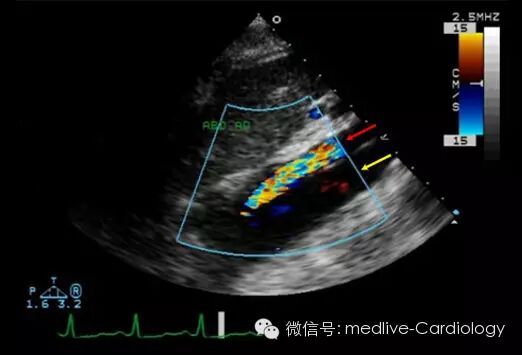

多普勒心脏彩超可以通过检测主动脉内血流存在与否来识别真腔(红色箭头)和假腔(黄色箭头)。超声同样可以用来评估心脏负荷、血管内膜撕裂部位的识别、夹层延长程度、心包积液和主动脉功能不全情况,尤其是对于升主动脉夹层的患者。